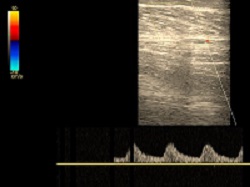

Miażdżycowe zwężenia tętnic.